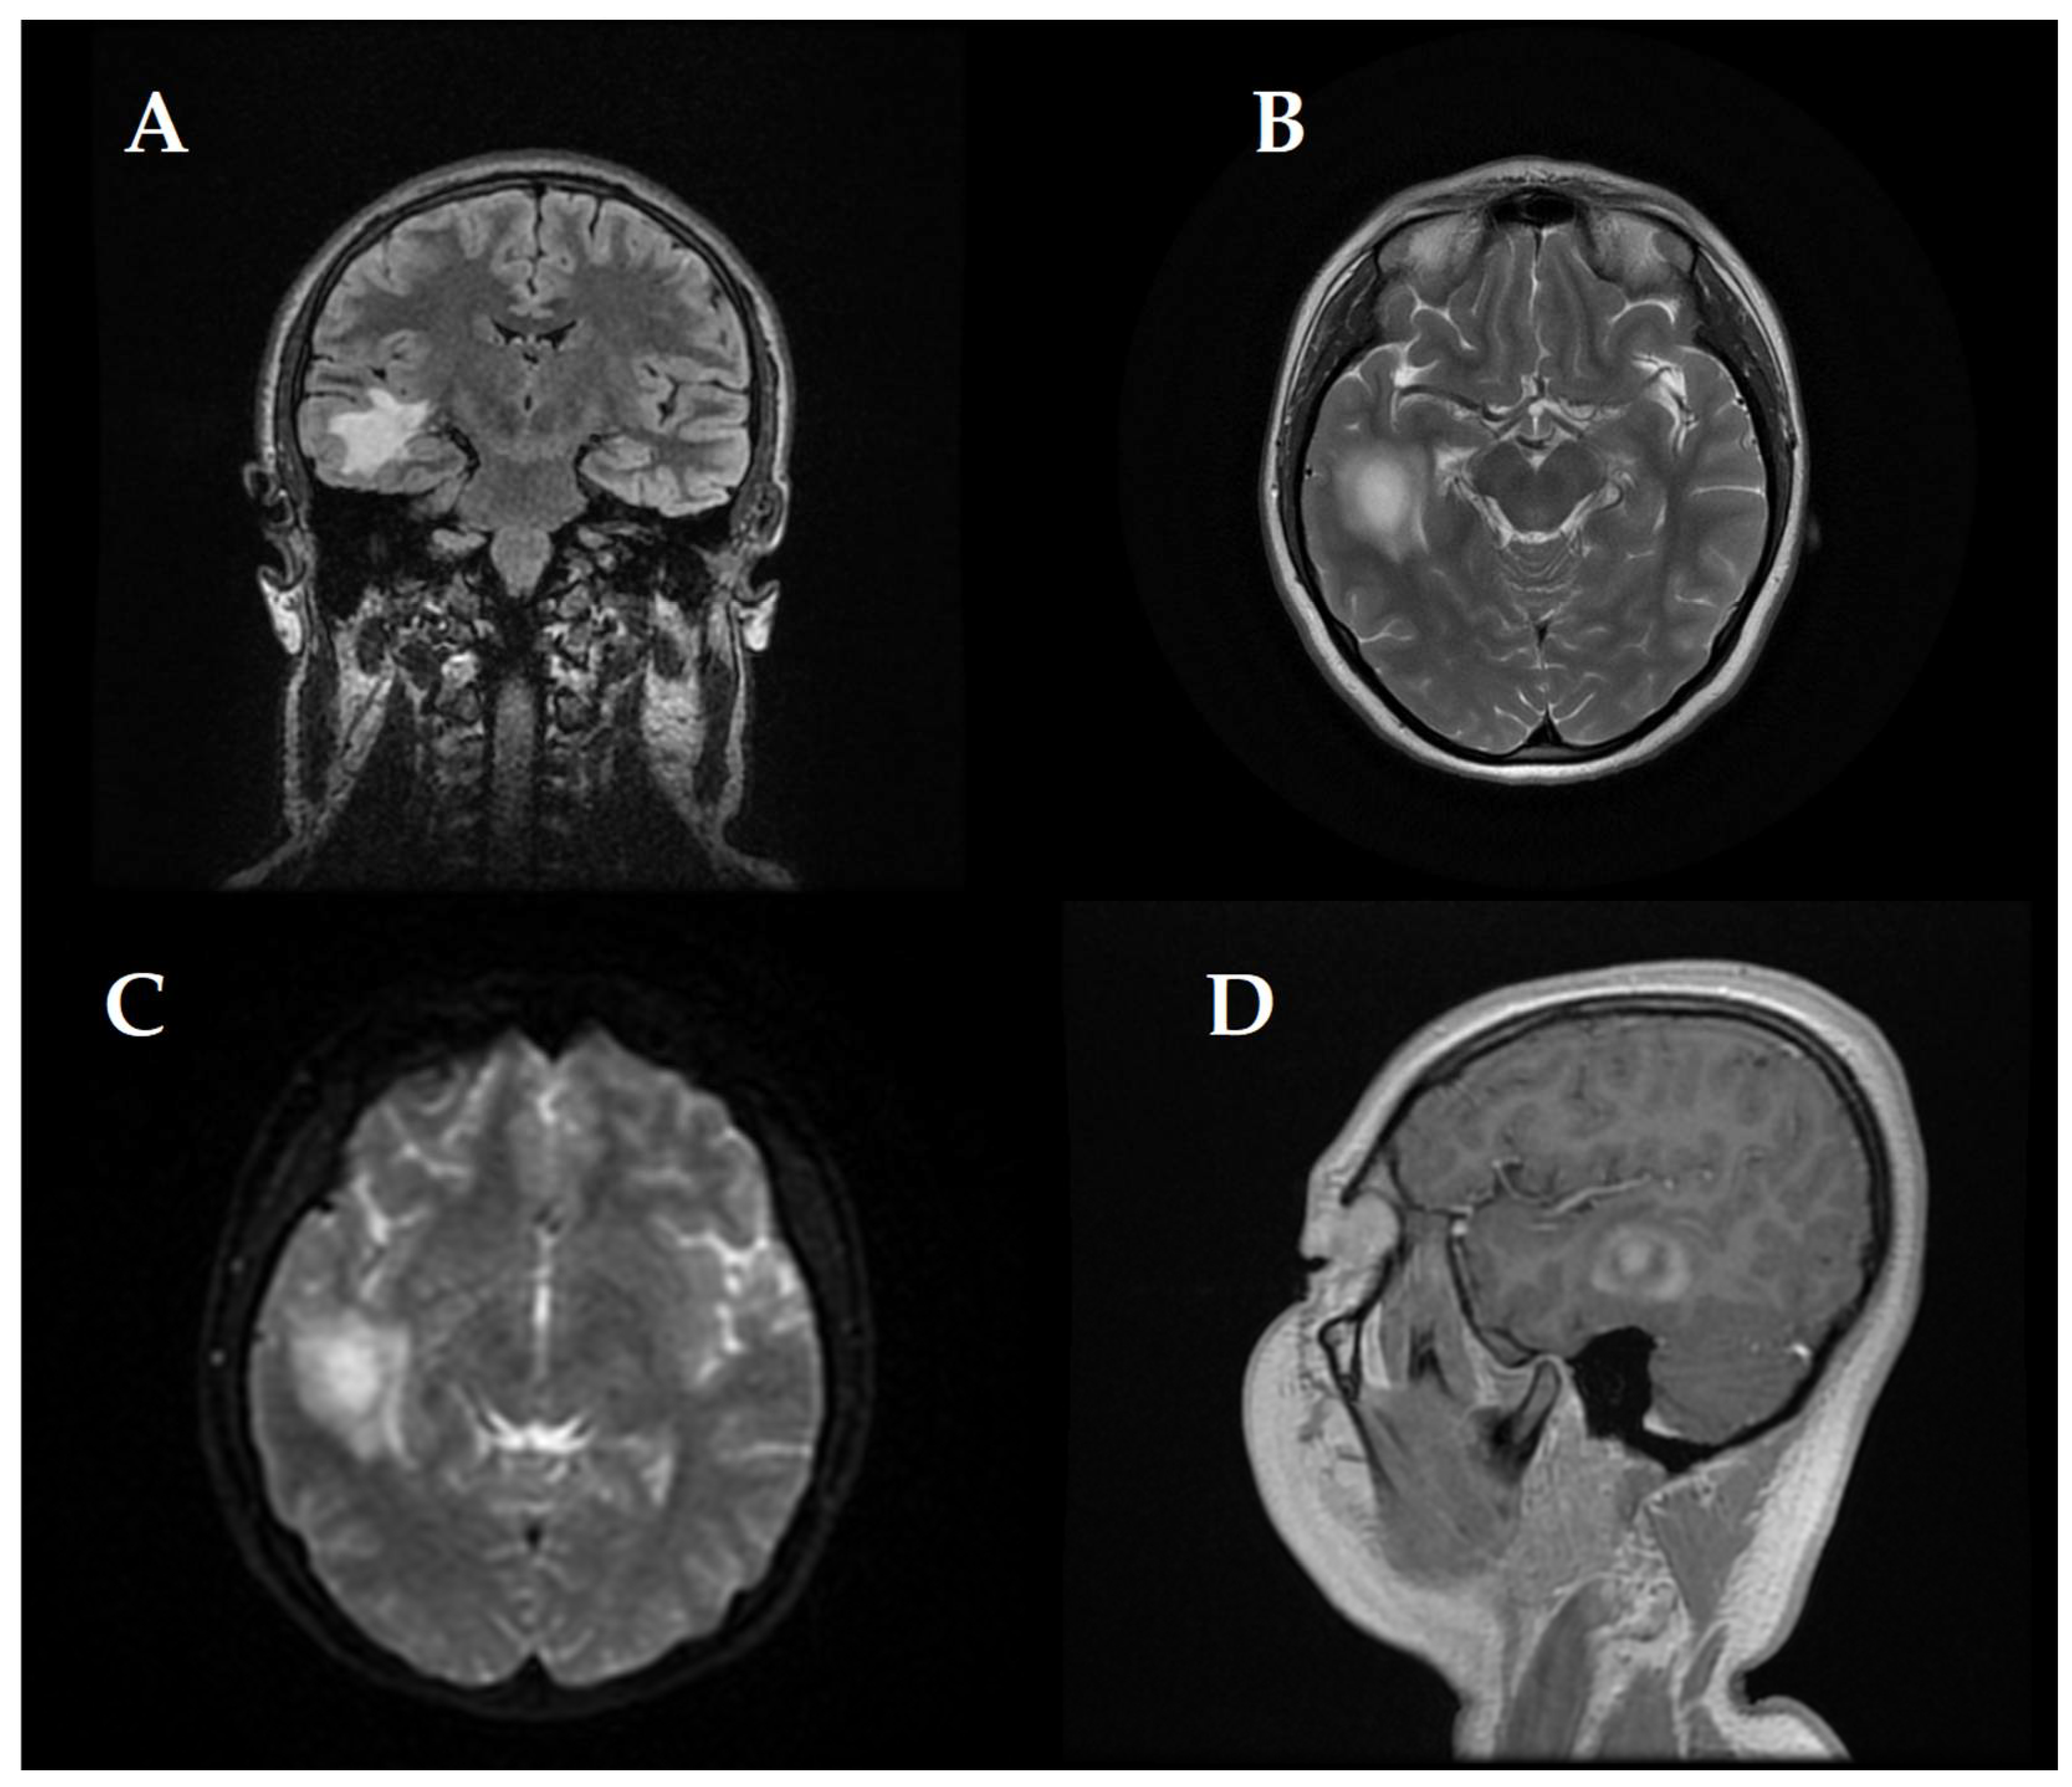

At first, clinical and neurological examination yielded no abnormalities. Then, the patient displayed signs of intracranial hypertension, which led to the decision to perform a brain MRI. The brain imaging showed a significant tumefactive demyelinating lesion located in the right temporal lobe with dimensions of 23 × 19 × 21.5 mm.

The lesion showed moderate perilesional vasogenic edema while demonstrating restricted diffusion and predominantly peripheral late gadolinium enhancement (Figure 1). The observed imaging pattern led the medical team to consider Baló’s concentric sclerosis-type lesion and glioma as potential diagnoses.

Figure 1. (AD) First MRI shows (A) Coronal FLAIR sequence right temporal lesion, characterized by moderate peripheral vasogenic edema, Axial T2-weighted imaging (B) confirms the extent of edema around the lesion, (C) Diffusion-weighted imaging (DWI) reveals restricted water diffusion and Sagittal post-contrast T1-weighted imaging (D) highlights predominantly late peripheral contrast enhancement measuring 23 × 19 × 21.5 mm.